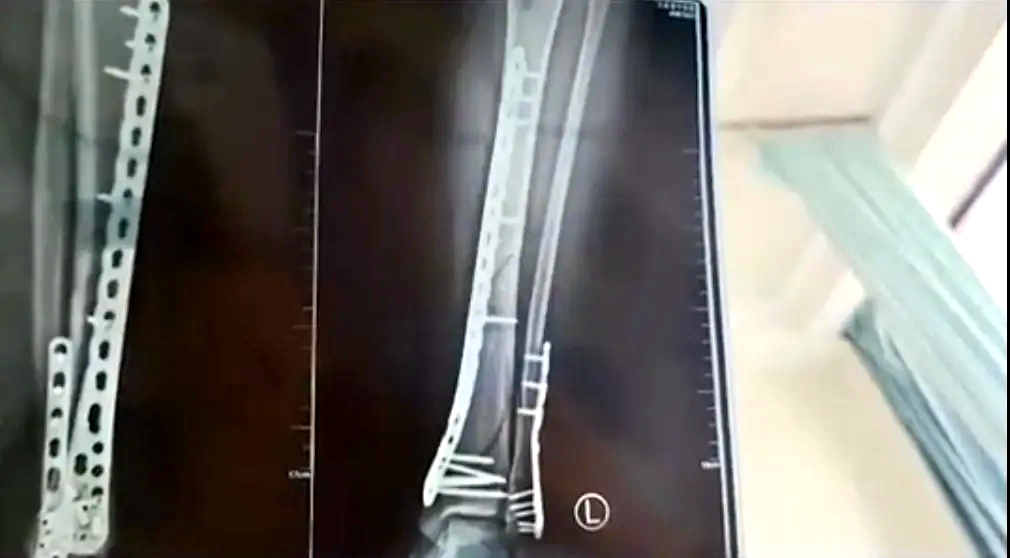

女子穿7cm厚洞洞鞋崴腳

致左腿粉碎性骨折

近日,甘肅蘭州的武女士稱母親節(jié)當(dāng)天,自己穿7cm厚洞洞鞋下樓,不慎崴腳摔倒,致使左腿粉碎性骨折。

武女士稱:因?yàn)槎炊葱男妆容^厚,腳掌中間又是凹進(jìn)去的,自己下樓梯的時候,正好踩到凹進(jìn)去的地方,當(dāng)時腳沒有踩穩(wěn),整個人的重心往前撲,所有重力都集中在腿上,結(jié)果就骨折了。

該女子稱,目前已做完手術(shù)在家休養(yǎng),不過下地得拄拐才行,且下地有時間限制,不能久站,而骨折完全康復(fù)可能需要3個月,她提醒大家穿增高鞋要注意。